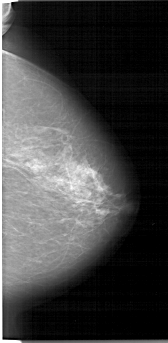

A_1335_1.LEFT_CC

LEFT_CC LINES 6706 PIXELS_PER_LINE 3421 BITS_PER_PIXEL 12 RESOLUTION 43.5 OVERLAY